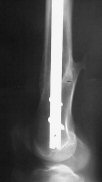

Attached are few examples from our Hospital:

B. Fixation loosening: distal cutting of the nail, non-unions do happen (cases attached).

Locking Plating has more distal screws than any nail, fixed angles and provides much better fixation, especially in osteoporotic bone.